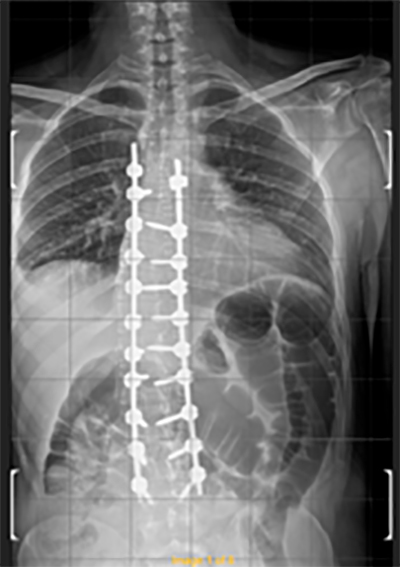

Intervento chirurgico eseguito:

Artrodesi dorso lombare con osteotomie correttive

Radiografia della colonna in toto post-operatoria